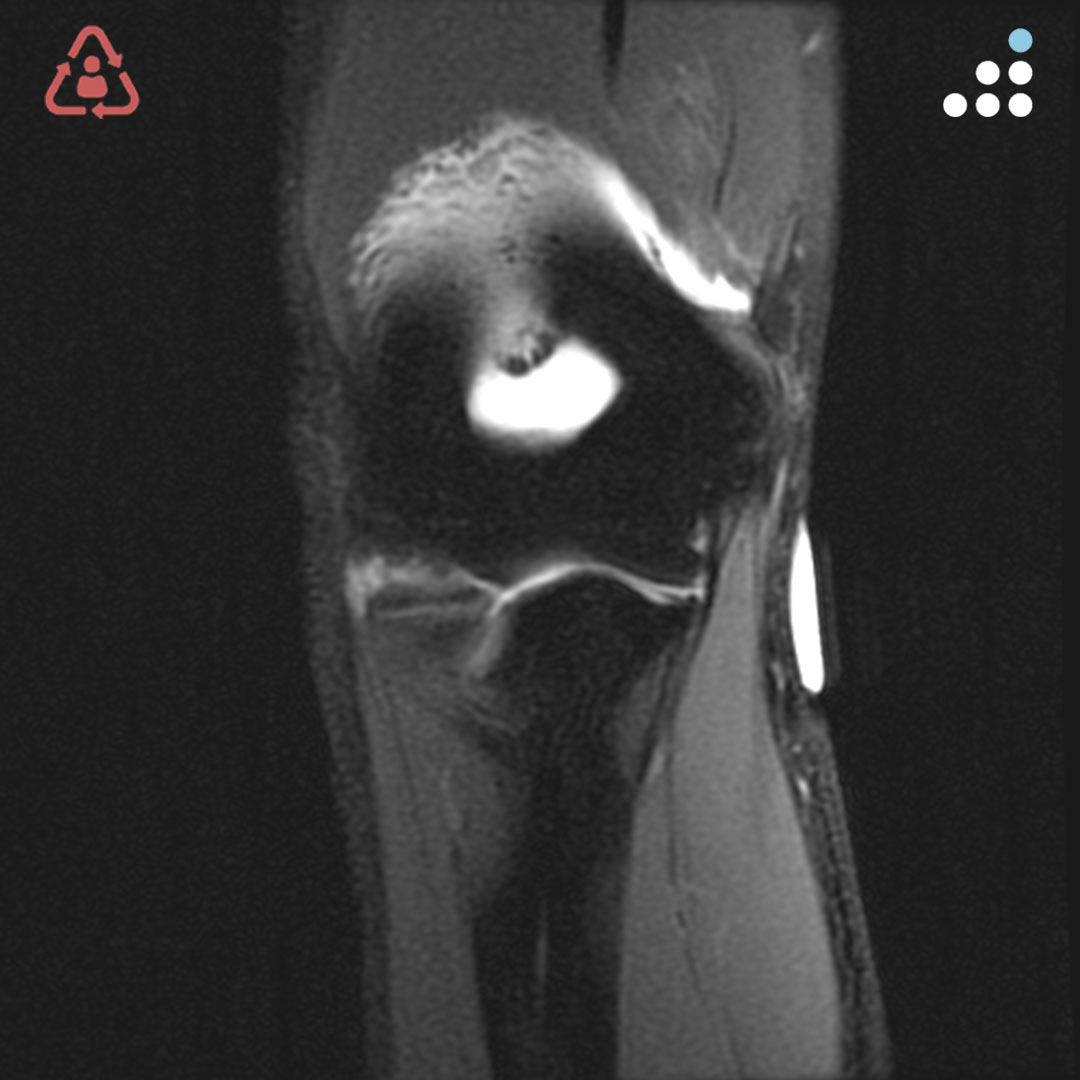

@orthobullets @KPSCALnews @rkh_md @DrMarecek @DeformityDoc @jamesablairMD @FractureDoc @stevemchale @traumaticum @DrFraneNicholas I am concerned about the +Fleck/flake sign. Get MRI or ultrasound to rule out a triceps rupture. If torn, I would perform ORIF and Triceps repair, after restoring the underlying metabolic issues. If the triceps is not torn, then would treat non-operatively.